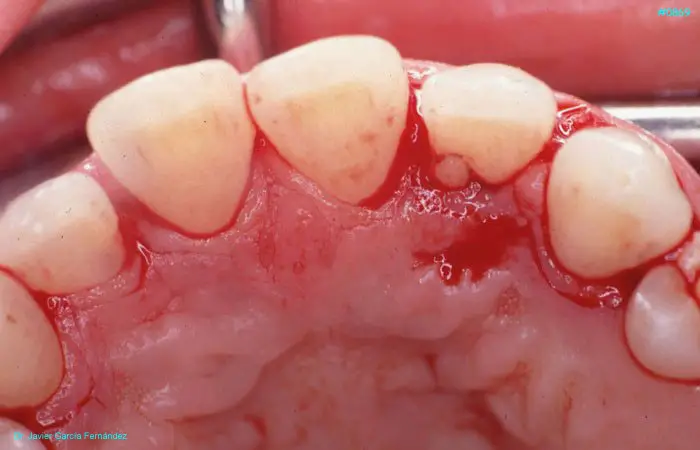

Atlas of Surgical Techniques in Periodontics. Chapter III. Atlas de Técnicas Quirúrgicas en Periodoncia